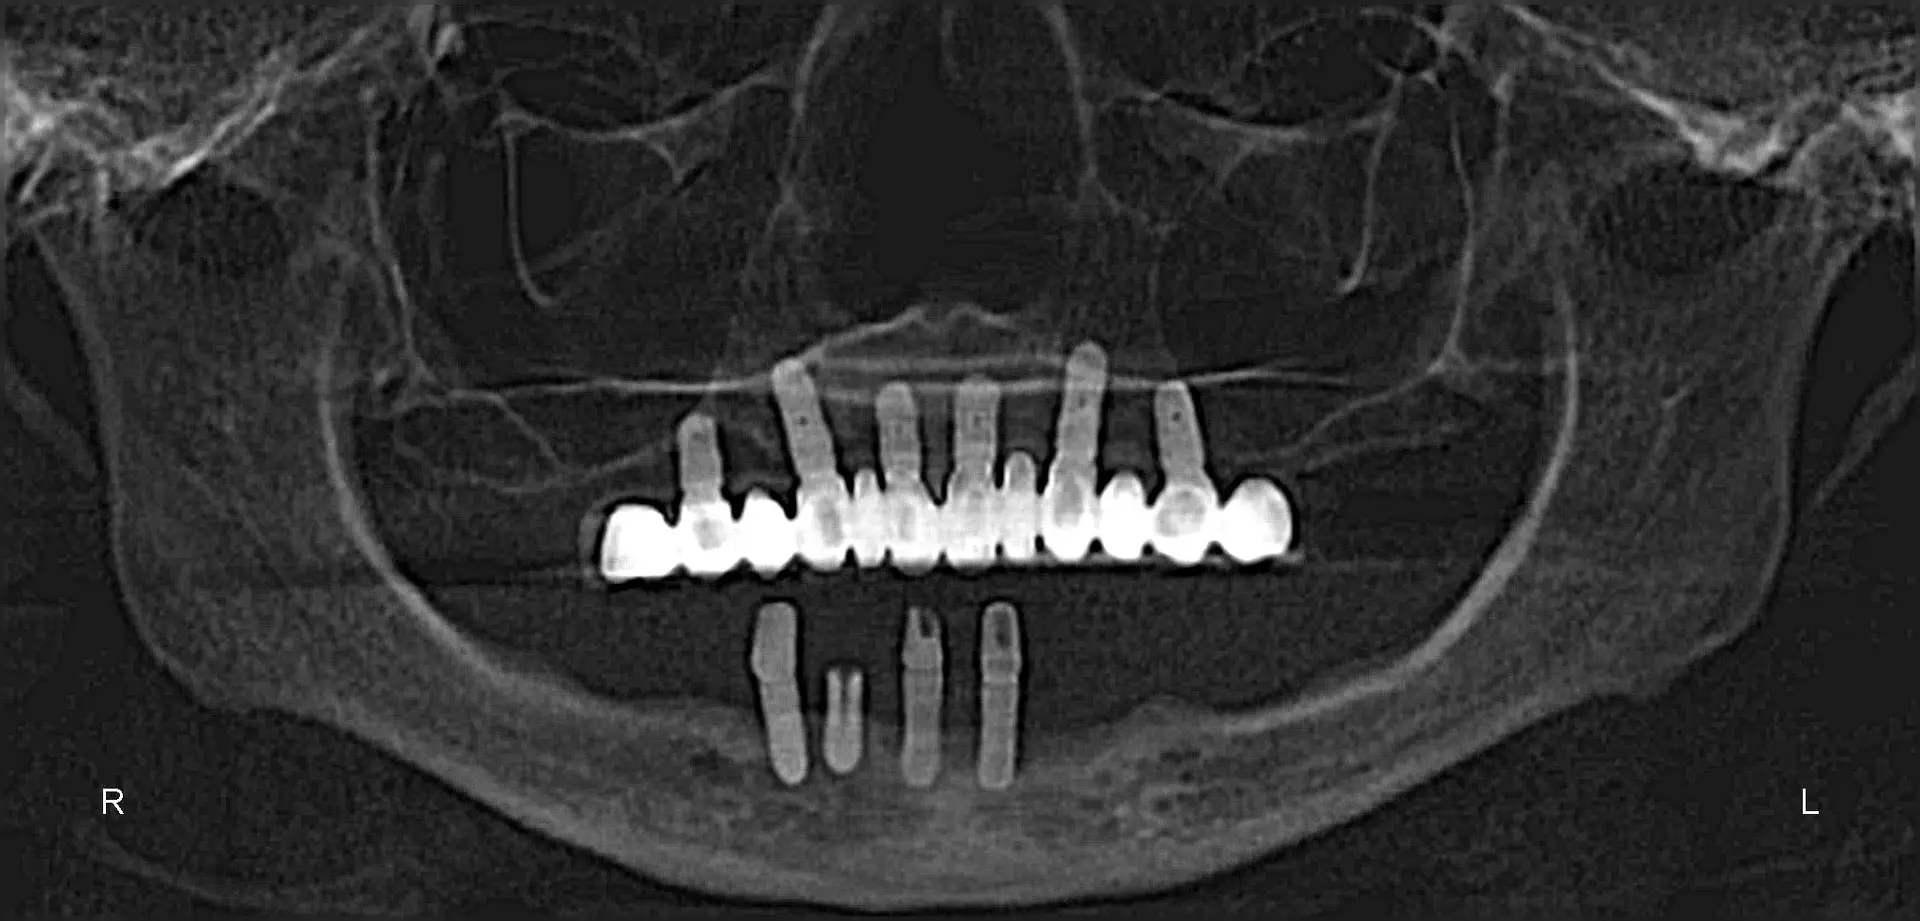

Documented case of Ana, a patient presenting with severe bone loss and failed implants. She was treated by our faculty member, Dr. Jay Neugarten, during the ZAGA Course as part of a live surgical demonstration for course participants. Treatment involved quad zygomatic implants and one pterygoid implant to improve stability. Using the ZAGA Approach, we were able to successfully rehabilitate the case despite the previous implant failures and deliver an immediate prosthesis on the same day as surgery. This case represents part of the clinical education and knowledge participants gain during the ZAGA course.